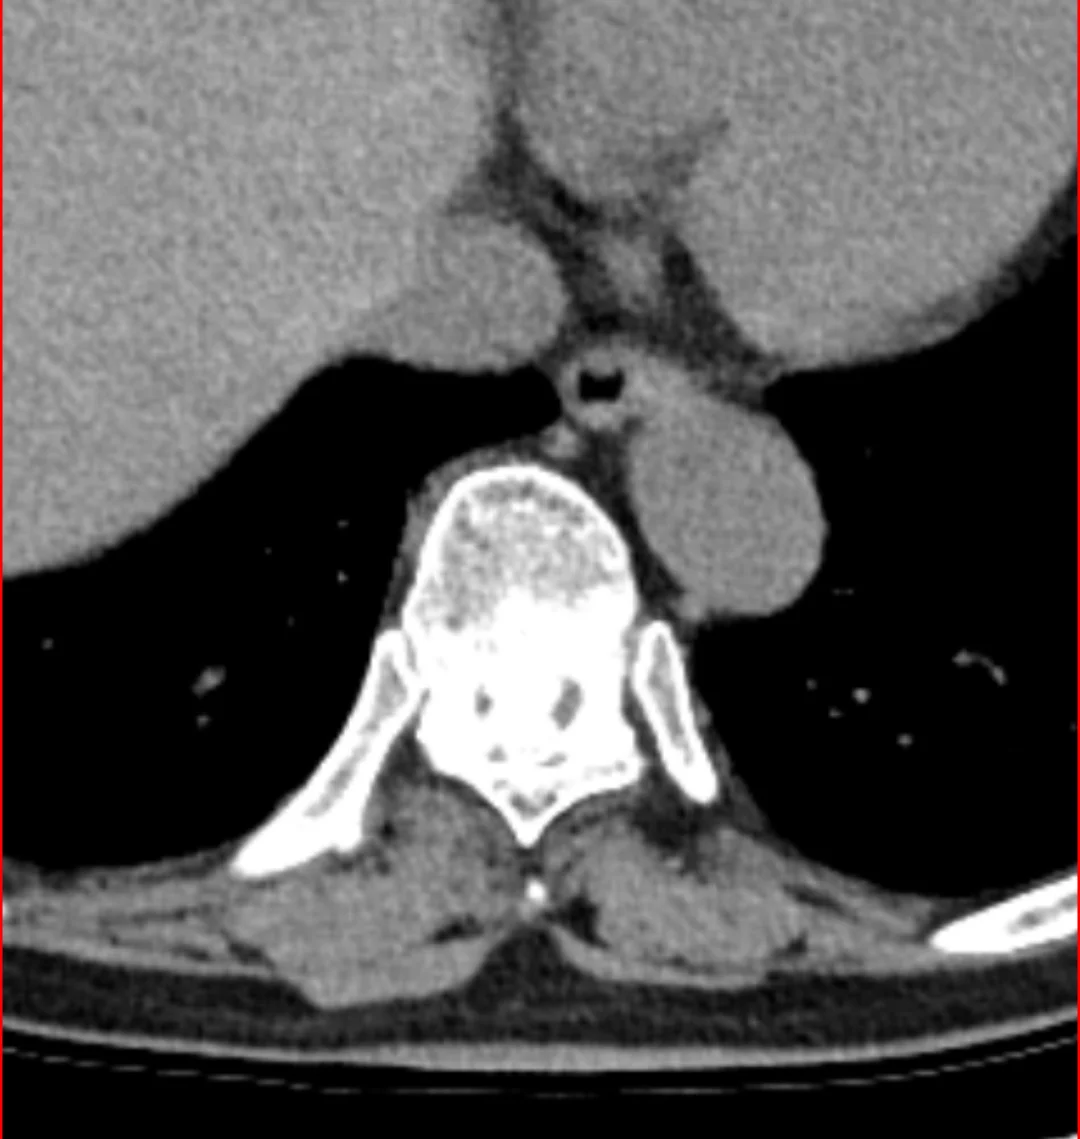

胸椎管狭窄微创

高风险 高瘫痪率胸椎管狭窄症